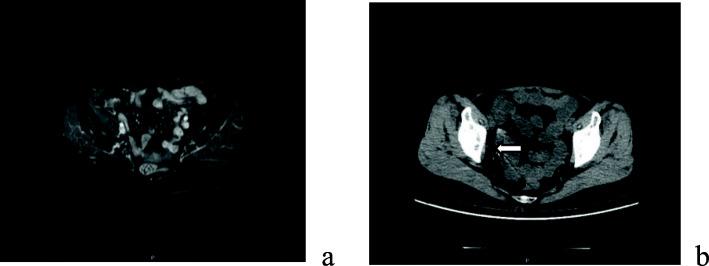

A 59-year-old woman presented with recurrent epithelial ovarian cancer who have had a history of ovarian cancer stage IIIB and an R0 resection had been achieved nearly 2 years before presented in our hospital. She underwent suboptimal secondary cytoreductive surgery after four cycles of chemotherapy with little effectiveness and severe chemotherapy-related side effects. Approximately 70% of the cancer-bulk was resected during surgery. For residual lesion which fixed around the right ureter and right external iliac vessel, I seeds implantation was performed. Postoperatively, the patient was treated with two cycles of combination chemotherapy with paclitaxel and carboplatin. The patient was free of disease at 26 months' follow-up period.

一名 59 岁女性因复发性上皮性卵巢癌就诊,该患者曾患有 IIIB 期卵巢癌,在近 2 年前于我院行卵巢癌 R0 切除术。在接受了四个周期的化疗(效果不佳且伴有严重的化疗相关副作用)后,她接受了次优的二次细胞减灭术。手术切除了约 70%的肿瘤肿块。对于固定在右侧输尿管和右侧髂外血管周围的残留病变,进行了 I 种子植入术。术后,患者接受了两个周期的紫杉醇联合卡铂联合化疗。在 26 个月的随访期间,患者无疾病。